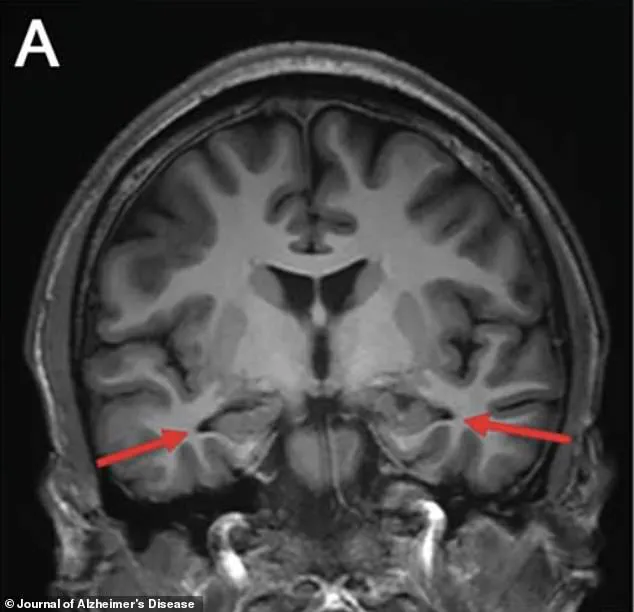

Brain scans conducted in 2022 revealed significant atrophy in the hippocampus, a region of the brain critical for memory formation and one of the first areas affected by Alzheimer’s disease.

This finding aligned with the clinical presentation of the condition but deepened the mystery of the patient’s case.

An MRI revealed alarming structural changes in the patient's brain.

The hippocampus, a critical region for memory formation, showed signs of early shrinkage.

Additional scans confirmed reduced activity in the parietal and temporal cortices, areas essential for cognitive processing and spatial awareness.

These findings painted a picture of progressive neural degeneration, though the cause remained unclear.